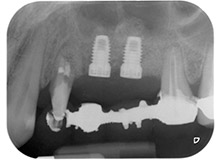

Фигури 17 и 18 показват клиничния резултат два месеца след операцията. Зъб 24 показва намалена подвижност на Милър клас 1 и меките тъкани не са възпалени. Сондирането е избегнато на този етап, за да се избегне повторно възпаление и нарушение на епителната надстройка. Планиран е контролен преглед за повторно отваряне и поставяне на оздравителни абатмънти, шест месеца след поставяне на имплантите.

На прегледа след два месеца, мобилността на останалия "дентален елемент" 24 вече е намалена от Милър 2 на Милър 1. Захващането на меките тъкани е на нивото на съседния зъб 23. Освен това, няма ендодонтски или периодонтални симптоми, така, че прогнозата трябва да се коригира.

Въпреки това, тъй като голяма част от букалната и проксималната кост липсва и композитното изграждане се простира до апикалната част корена, не се очаква по-високо ниво на захващане в следствие на биологични причини (Sculean et al., 2008).

Подът на синуса и GBR процедурите вероятно ще доведат до алвеоларна подкрепа на имплантите и добра прогноза (Retzepi and Donus, 2010, Calin et al., 2014). След остеоинтеграция, имплантите в позиция 25 и 26 ще бъдат възстановени с шинирана корона. Ако някой от зъбите трябва да бъде екстрахиран, той ще бъде заместен от единично поставяне на имплант с корона.